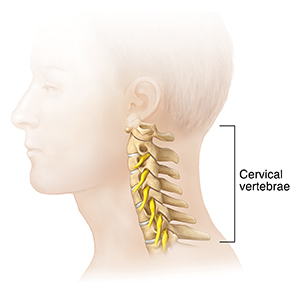

The cervical bones (vertebrae) are the top seven bones of your spine. They are located along your neck, just below the skull. Fusing vertebrae in the neck may help ease neck and arm pain. It may also help relieve progressive paralysis caused by compression of your nerve roots or spinal cord. Two or more vertebrae in your neck are fused. Fusion may be done through a cut in the front or the back of the neck. The surgery can take from 1 to 4 hours.